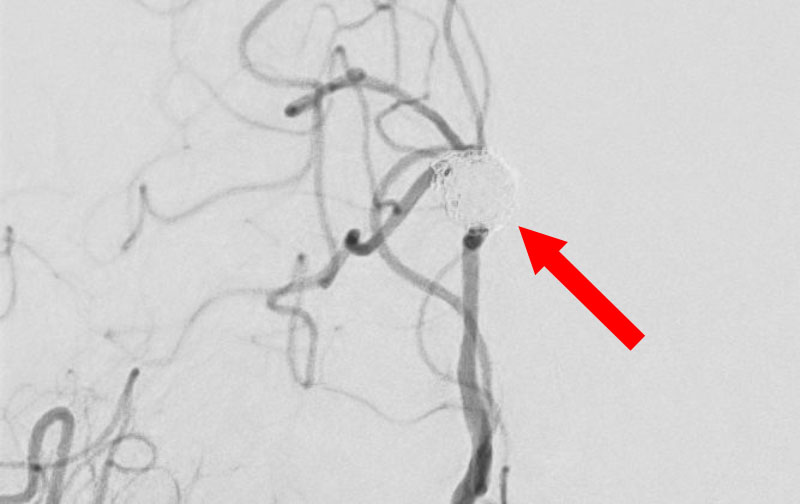

左内頚動脈脳動脈瘤

60代

大阪府の病院

No.1595 手術前

No.1595 手術中

No.1595 手術後